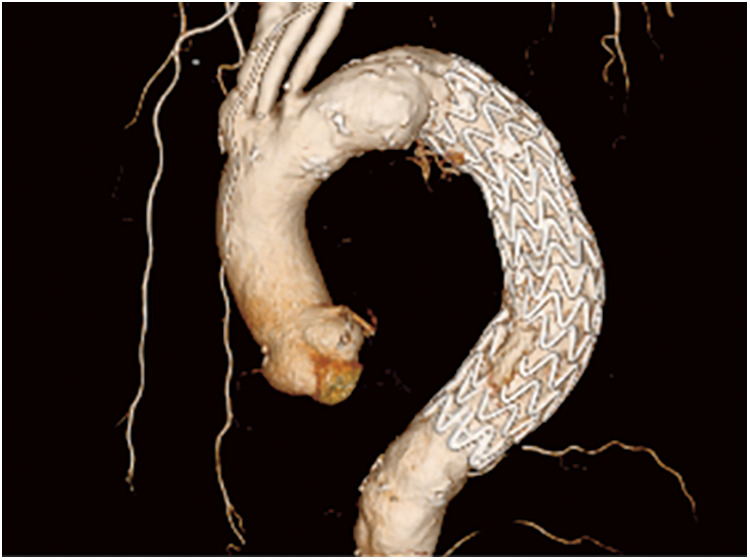

胸主动脉瘤(TAAs)的胸腔内血管主动脉修复术(TEVAR)是高风险患者的另一种治疗选择。虽然传统上是通过经胸途径进行,但有时由于入路不畅而难以实施。我们报告了一例 90 岁男性患者的病例,他在接受食道癌计算机断层扫描时意外被诊断出患有降支 TAA。患者曾接受过两次 Y 型移植物置换术。他的 Y 型移植物腿角度很大,因此经股动脉入路被认为是困难的。因此,患者接受了经心尖 TEVAR 手术。术后恢复顺利。经心尖 TEVAR 是治疗超高龄患者入路不畅的 TAAs 的有效方法。

Thoracic endovascular aortic repair (TEVAR) for thoracic aortic aneurysms (TAAs) is an alternative treatment option for high-risk patients. While conventionally performed via a transfemoral approach, it is sometimes difficult due to poor access routes. We report the case of a 90-year-old man who was incidentally diagnosed with a descending TAA while undergoing computed tomography for esophageal cancer. The patient had undergone Y-graft replacement twice. His Y-graft leg was highly angulated; therefore, a transfemoral approach was considered difficult. Consequently, transapical TEVAR was performed. The postoperative course was uneventful. Transapical TEVAR can be a useful treatment option for TAAs with poor access routes in super-old patients.